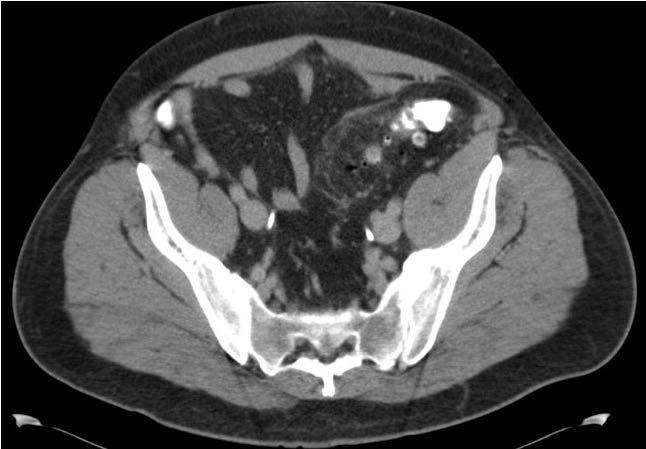

体格检查,体温升高到39.4℃,血压130/76mmHg,脉搏110次/分,呼吸20次/分,非急性窘迫,但有轻微的出汗。口咽清晰,有粘膜干燥。肺部听诊清音,心率正常,无杂音。 腹部检查显示左下象限中度压痛,有腹壁紧张。无反跳痛。无脊肋角压痛,未见腹股沟疝,生殖器检查结果均正常。直肠指诊,左侧直肠穹隆柔软,愈创木脂阴性。其余体检结果无异常。 血清实验室检测仅白细胞升高,为16×103/µL,其中中性粒细胞显著,尿检无异常。标准拍摄腹部平片,未见任何明显异常。后进行腹部和骨盆的CT

急性憩室炎由继发于粪便梗阻的憩室发炎引起。梗阻通常发生在憩室颈部;凝固的粪便,通常形成粪石,损伤黏憩室颈部哪内外黏膜。 在无并发症的情况下(典型的是患者没有出现腹膜炎及全身症状),炎症过程局限于结肠壁;然而,梗阻,随着憩室腔内高压,可以导致微小穿孔,反过来引起细菌通过结肠壁移位,脓肿形成,弥漫性腹膜炎。